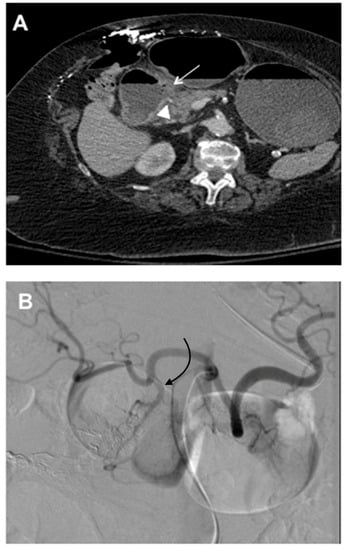

3. GDA Embolization in Gastrointestinal Bleeding

4. GDA Pseudoaneurysm Embolization